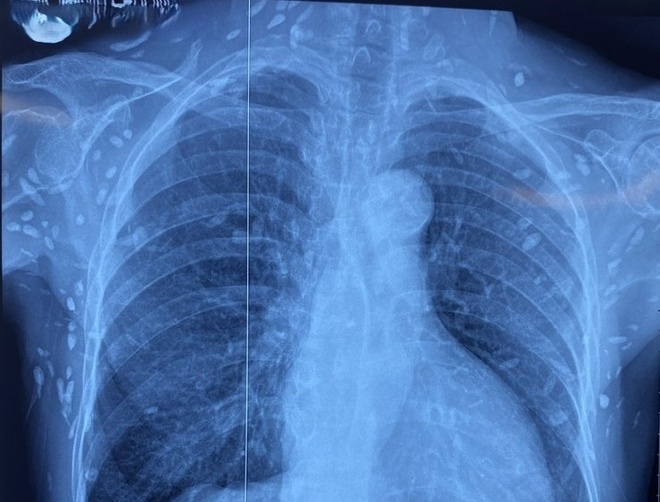

| Nhiều nốt cản quang dưới da thành ngực - bụng của bệnh nhân do sán dây lợn. Ảnh: BVCC |

Một dạng khác là bệnh "gạo người", khi trứng sán nở ra ấu trùng và di chuyển đến các cơ quan khác trong cơ thể. "Tùy vị trí ký sinh mà biểu hiện khác nhau. Nếu ở não, người bệnh có thể bị đau đầu, co giật, yếu liệt tay chân, rối loạn thị giác. Nếu ở cơ, có thể đau nhức, nổi cục nhỏ dưới da", bác sĩ Minh cho biết.